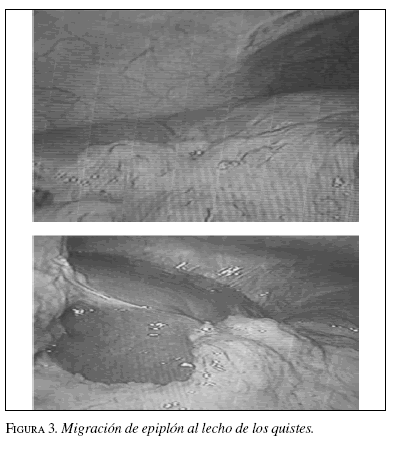

Después de resecar el techo de los quistes, debido a la cantidad del líquido drenado y teniendo en cuenta que no se fijó epiplón en su interior, se dejaron sendos drenes, para evaluar las características del líquido que pudiera drenar y evitar su acumulación en caso de ser bilioso. En el control laparoscópico se observó la migración del epiplón hasta el lecho de estos quistes y su incorporación a los mismos (figura 3).